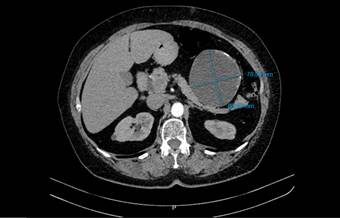

Se realizó una ecografía de abdomen total que informó una imagen quística de 8 x 7 cm, en íntimo contacto con la cola del páncreas. Posteriormente una tomografía computarizada de abdomen con contraste reportó una lesión hipodensa de aspecto quístico, de 86,6 x 78,5 mm, en contacto con la curvatura mayor del estómago, el cuerpo y la cola del páncreas, con paredes irregularmente engrosadas y calcificaciones periféricas aisladas en su interior. Como primera posibilidad se sugirió un tumor del estroma gastrointestinal (GIST, por sus siglas en inglés) (figuras 1 y 2). La endoscopia de vías digestivas altas diagnosticó una gastropatía antrocorporal no erosiva sin hallazgos patológicos adicionales.

Figura 1. Corte axial de tomografía computarizada contrastada de abdomen (plano transverso). Se señala la lesión hipodensa de aspecto quístico de 86.6 mm x 78.5 mm.